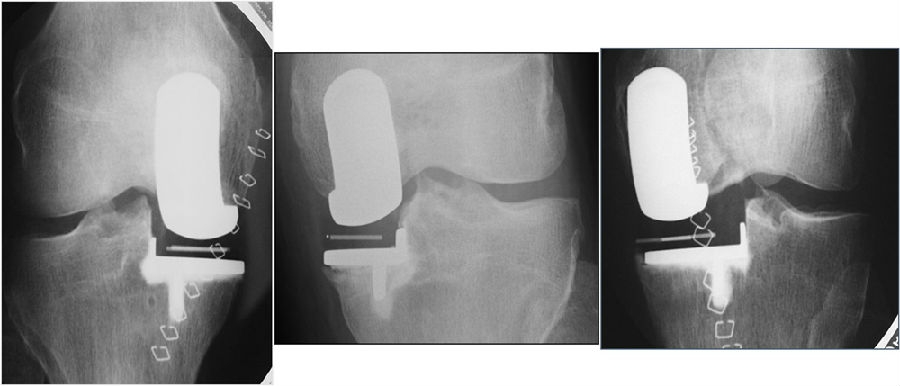

冠状面对线:单髁术后冠状位对线不是由股骨假体和胫骨假体放置的内外翻决定的,而是由垫片厚度和紧张度决定的。选择可以恢复韧带张力的衬垫厚度,将下肢力线情况恢复到疾病前状态。

不取决于假体组件的对线情况(cf TKR)。假体组件为球形。允许出现少许对线不良。

股骨侧截骨的目标是重建正常关节线,通过韧带平衡确定植入假体的远端位置,进行截骨,直到屈伸间隙相等,屈曲和伸直运动中的韧带张力相同。